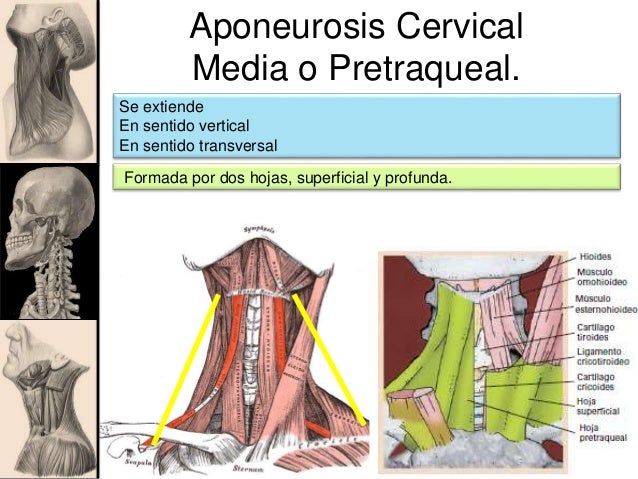

También se relaciona con la hoja superficial de la fascia cervical, que se dirige transversalmente desde un esternocleidomastoideo hasta el otro, esta limita con la horquilla esternal al espacio de Gruber, esta se encuentra perforada en su parte media por las venas yugulares anteriores, que van de un plano superficial a un plano profundo.

Hoja pretraqueal de la fascia cervical, que se encuentra unida con la hoja superficial, se extiende de manera transversal, del musculo omohioideo al omohioideo del lado opuesto, envolviendo a los esternocleidomastoideos.